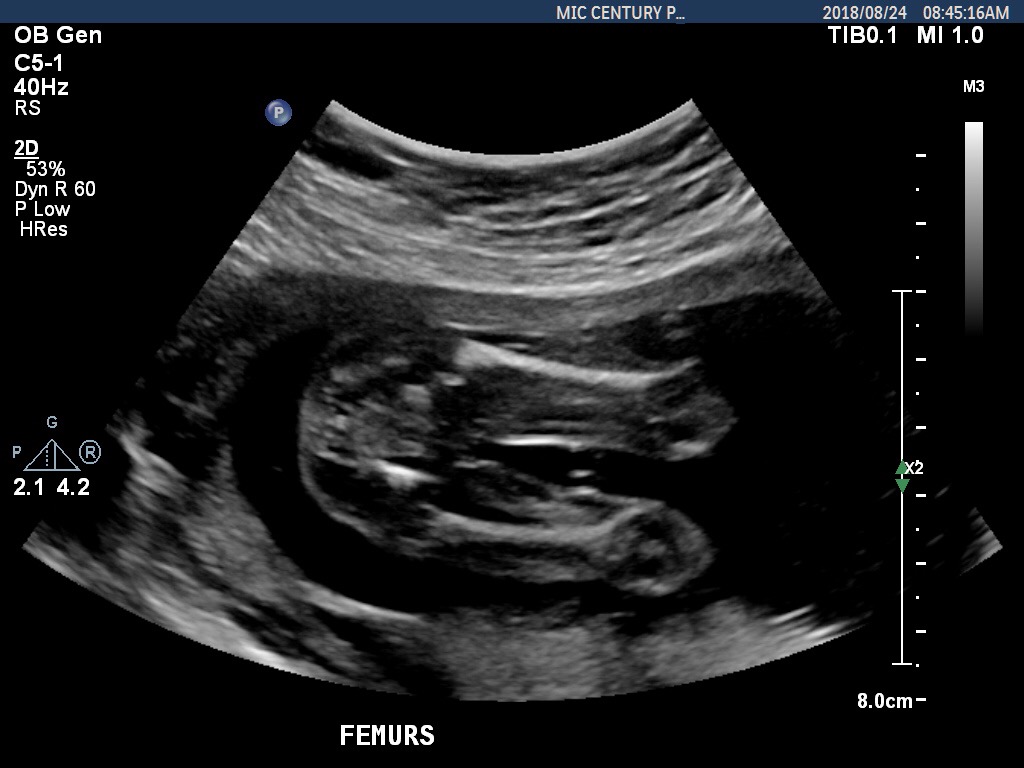

There are no gender clues in this picture unless you maybe wanted to go by skull shape but I don't buy into that theory.

I would say girl based on the potty shot.

the potty shot looks girly, nothing between the legs in that particular shot. goodluck :)

Thanks. I really don’t know what I’m looking at. Thought maybe there was something.